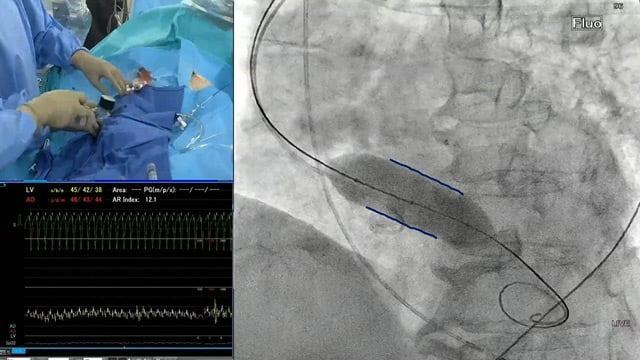

Coronary access and revascularisation in patients undergoing TAVI: from work-up to lifetime management

15 Feb 2026 – From PCR Tokyo Valves 2026

This session delves into the comprehensive management of ischemic heart disease in patients undergoing transcatheter aortic valve implantation (TAVI). It highlights the critical importance of maintaining coronary access post-TAVI and explores how various valve designs affect coronary accessibility, particularly in cases involving valve-in-valve (TAV-in-TAV) procedures, guiding...